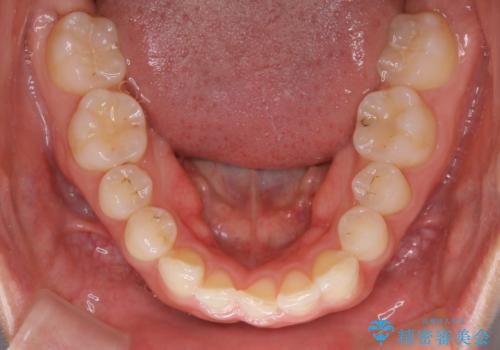

【非抜歯】下の前歯が1本少ない場合の矯正治療

- 前歯のガタつきを主訴に来院されました。

生まれつき下の前歯が1本少なく、その分のスペースを上の前歯がガタつくことで埋めているという状況でした。

上下それぞれのガタつきをとっていく過程で、歯1本分のスペースの差を、上顎の前歯のIPRで調整して並べる方法をご提案させていただきました。

稀に、乳歯が抜けてもその後に永久歯が生えてこないことがあります。生まれつき歯の元となる「歯胚」というものが欠如していることが原因で本数が少なくなることを「先天欠如」といいます。

こういったケースの治療では欠損している歯の本数分反対の顎の歯(上顎に欠損がある場合は下顎の歯)を抜歯してスペースの調整をする場合や、欠損歯の幅分のIPRを反対の顎の歯に設定することでスペースのコントロールをするという方法、欠損している歯の分のスペースを残して矯正を終了し最後にブリッジ治療やインプラントで歯の本数を増やすという方法があり、状況や患者さんの希望により選択をしていきます。